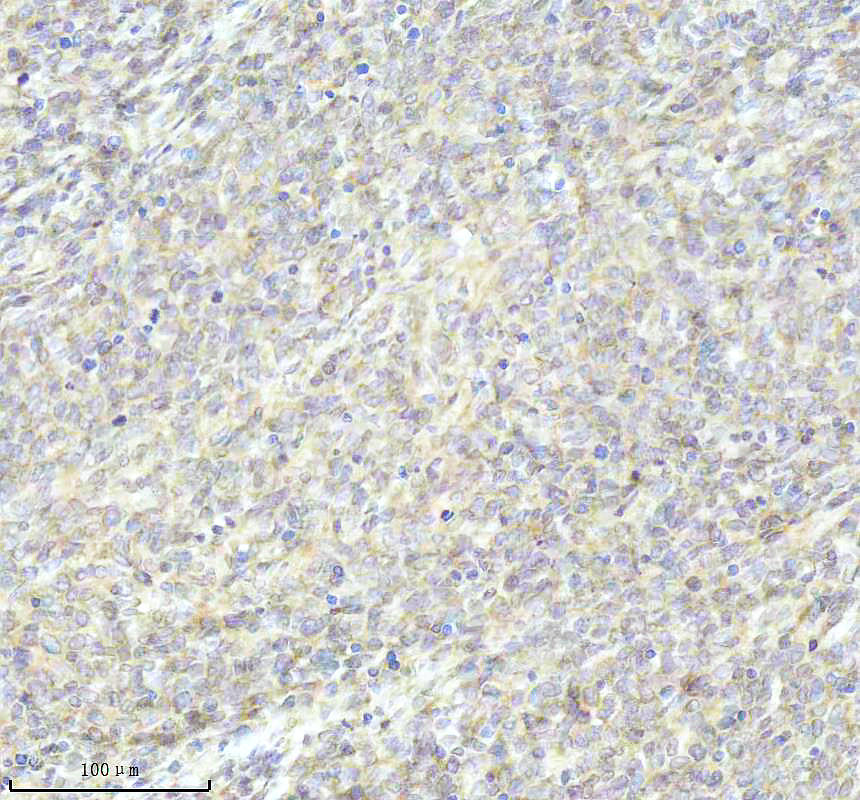

IHC analysis of BNIP3L using anti-BNIP3L antibody (BM5174) .

BNIP3L was detected in a paraffin-embedded section of human lymphoma tissue. The tissue section was incubated with rabbit anti-BNIP3L Antibody (BM5174) at a dilution of 1:200 and developed using HRP Conjugated Rabbit IgG Super Vision Assay Kit (Catalog # SV0002) with DAB (Catalog # AR1027) as the chromogen.

IHC analysis of BNIP3L using anti-BNIP3L antibody (BM5174) .

BNIP3L was detected in a paraffin-embedded section of human lymphoma tissue. The tissue section was incubated with rabbit anti-BNIP3L Antibody (BM5174) at a dilution of 1:200 and developed using HRP Conjugated Rabbit IgG Super Vision Assay Kit (Catalog # SV0002) with DAB (Catalog # AR1027) as the chromogen.